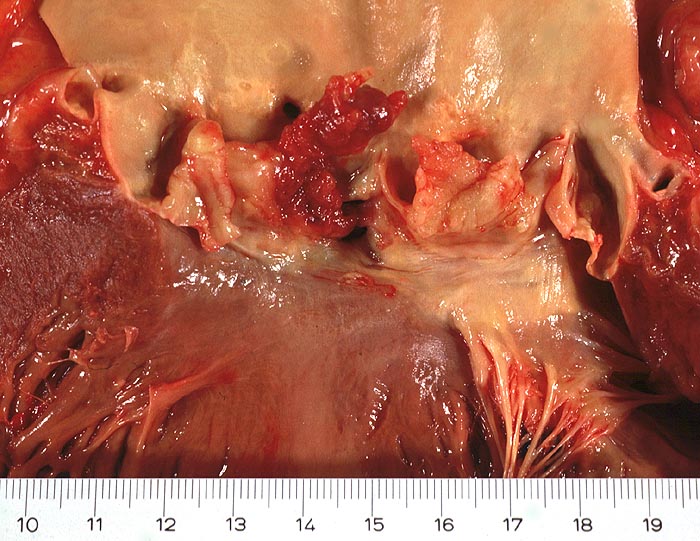

Makroskopisch sind entweder flache rötliche fibrinbelegte Ulzera (=ulcerosa (> 2935)) oder zusätzlich weiche gelbbraune bröcklige erbs- bis pflaumengrosse Polypen (=ulceropolyposa (> 2936) (> 8376)) oder ausschliesslich polypoide Fibrinbeläge (=marantica) auf einem Endokarddefekt oder einer partiell zerstörten Klappe erkennbar.

• Längsschnitt durch Aorta, Aortenklappe und linkes Ventrikelmyokard.

• Oben im Bild die Aorta mit kleinem Fibroatherom.

• Abszedierende Entzündung der aortalen Adventitia ausgehend von septikopyämischen Streuherden.

• Ulzerierte Aortenklappe(ulcerosa).

• Dem ulzerierten Klappengerüst aufgelagerte polypöse Vegetation aus Fibrin und Granulozyten durchsetzt von blauen Kokkenbakterienkolonien (polyposa).